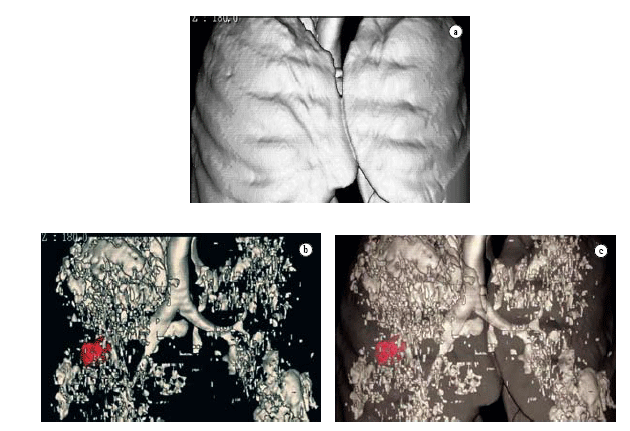

The acquisition of data volume in a single breath-hold allows us to reconstruct data in three-dimensional format, using three-dimensional CT. This technological resource has been more frequently used in the investigation of chest alterations.(51-56) One of the pioneers in the dissemination of the technique(56) demonstrated its efficiency in the quantification of emphysema. The denomination three-dimensional CT-guided densitometry and volumetric assessment for emphysema(55) has been currently suggested for this quantification process of the volume of emphysema, based on data obtained through spiral CT scan with three-dimensional representation of emphysematous lesions (Figures 5 and 6). The test measures the whole pulmonary volume with abnormal density and, also, the whole lung volume with normal density,(41,56-61) setting them apart based on the separation threshold generally selected at −950 HU, as per the suggestion of one author. Among the practical applications of the technique, one study demonstrated that normal CT-guided pulmonary densitometry and volumetric assessment excels HRCT, and should be included in the preoperative evaluation of patients for whom surgery for volumetric reduction of the lungs has been indicated.(58) This clinical applicability of three-dimensional CT-guided densitometry and volumetric assessment used for the same purpose has been known in Brazil for some time.(39) In a recent consensus, the use of three-dimensional CT-guided densitometry and volumetric assessment was suggested for the evaluation of therapeutic efficacy in the treatment of emphysema, replacing FEV.(59)

The evaluation of advantages of three-dimensional CT-guided densitometry and volumetric assessment for therapeutic decision in patients with operable pulmonary carcinoma from the point of view of tumor-node-metastasis staging is under study. However, with borderline pulmonary function. Figure 7 exemplifies a case in which the

neoplastic lesion (in red) is found, by unfortunate and common chance, in the lobe that was less affected by emphysema. In this case, lower right lobectomy will be almost equivalent to pneumonectomy, since the right upper lobe, which would be the remaining lobe, is almost completely compromised by emphysema.

With the establishment of normality reference values,(55) it is already possible, as well, to use three-dimensional CT-guided densitometry and volumetric assessment in the early diagnosis and graduation of the severity of the disease, and this early detection and demonstration of three-dimensional imaging to the patient has been suggested as potentially useful in techniques of smoking cessation.(60) In addition, it also seems promising in the evaluation of patients whose occupational activities can induce the development of emphysema.